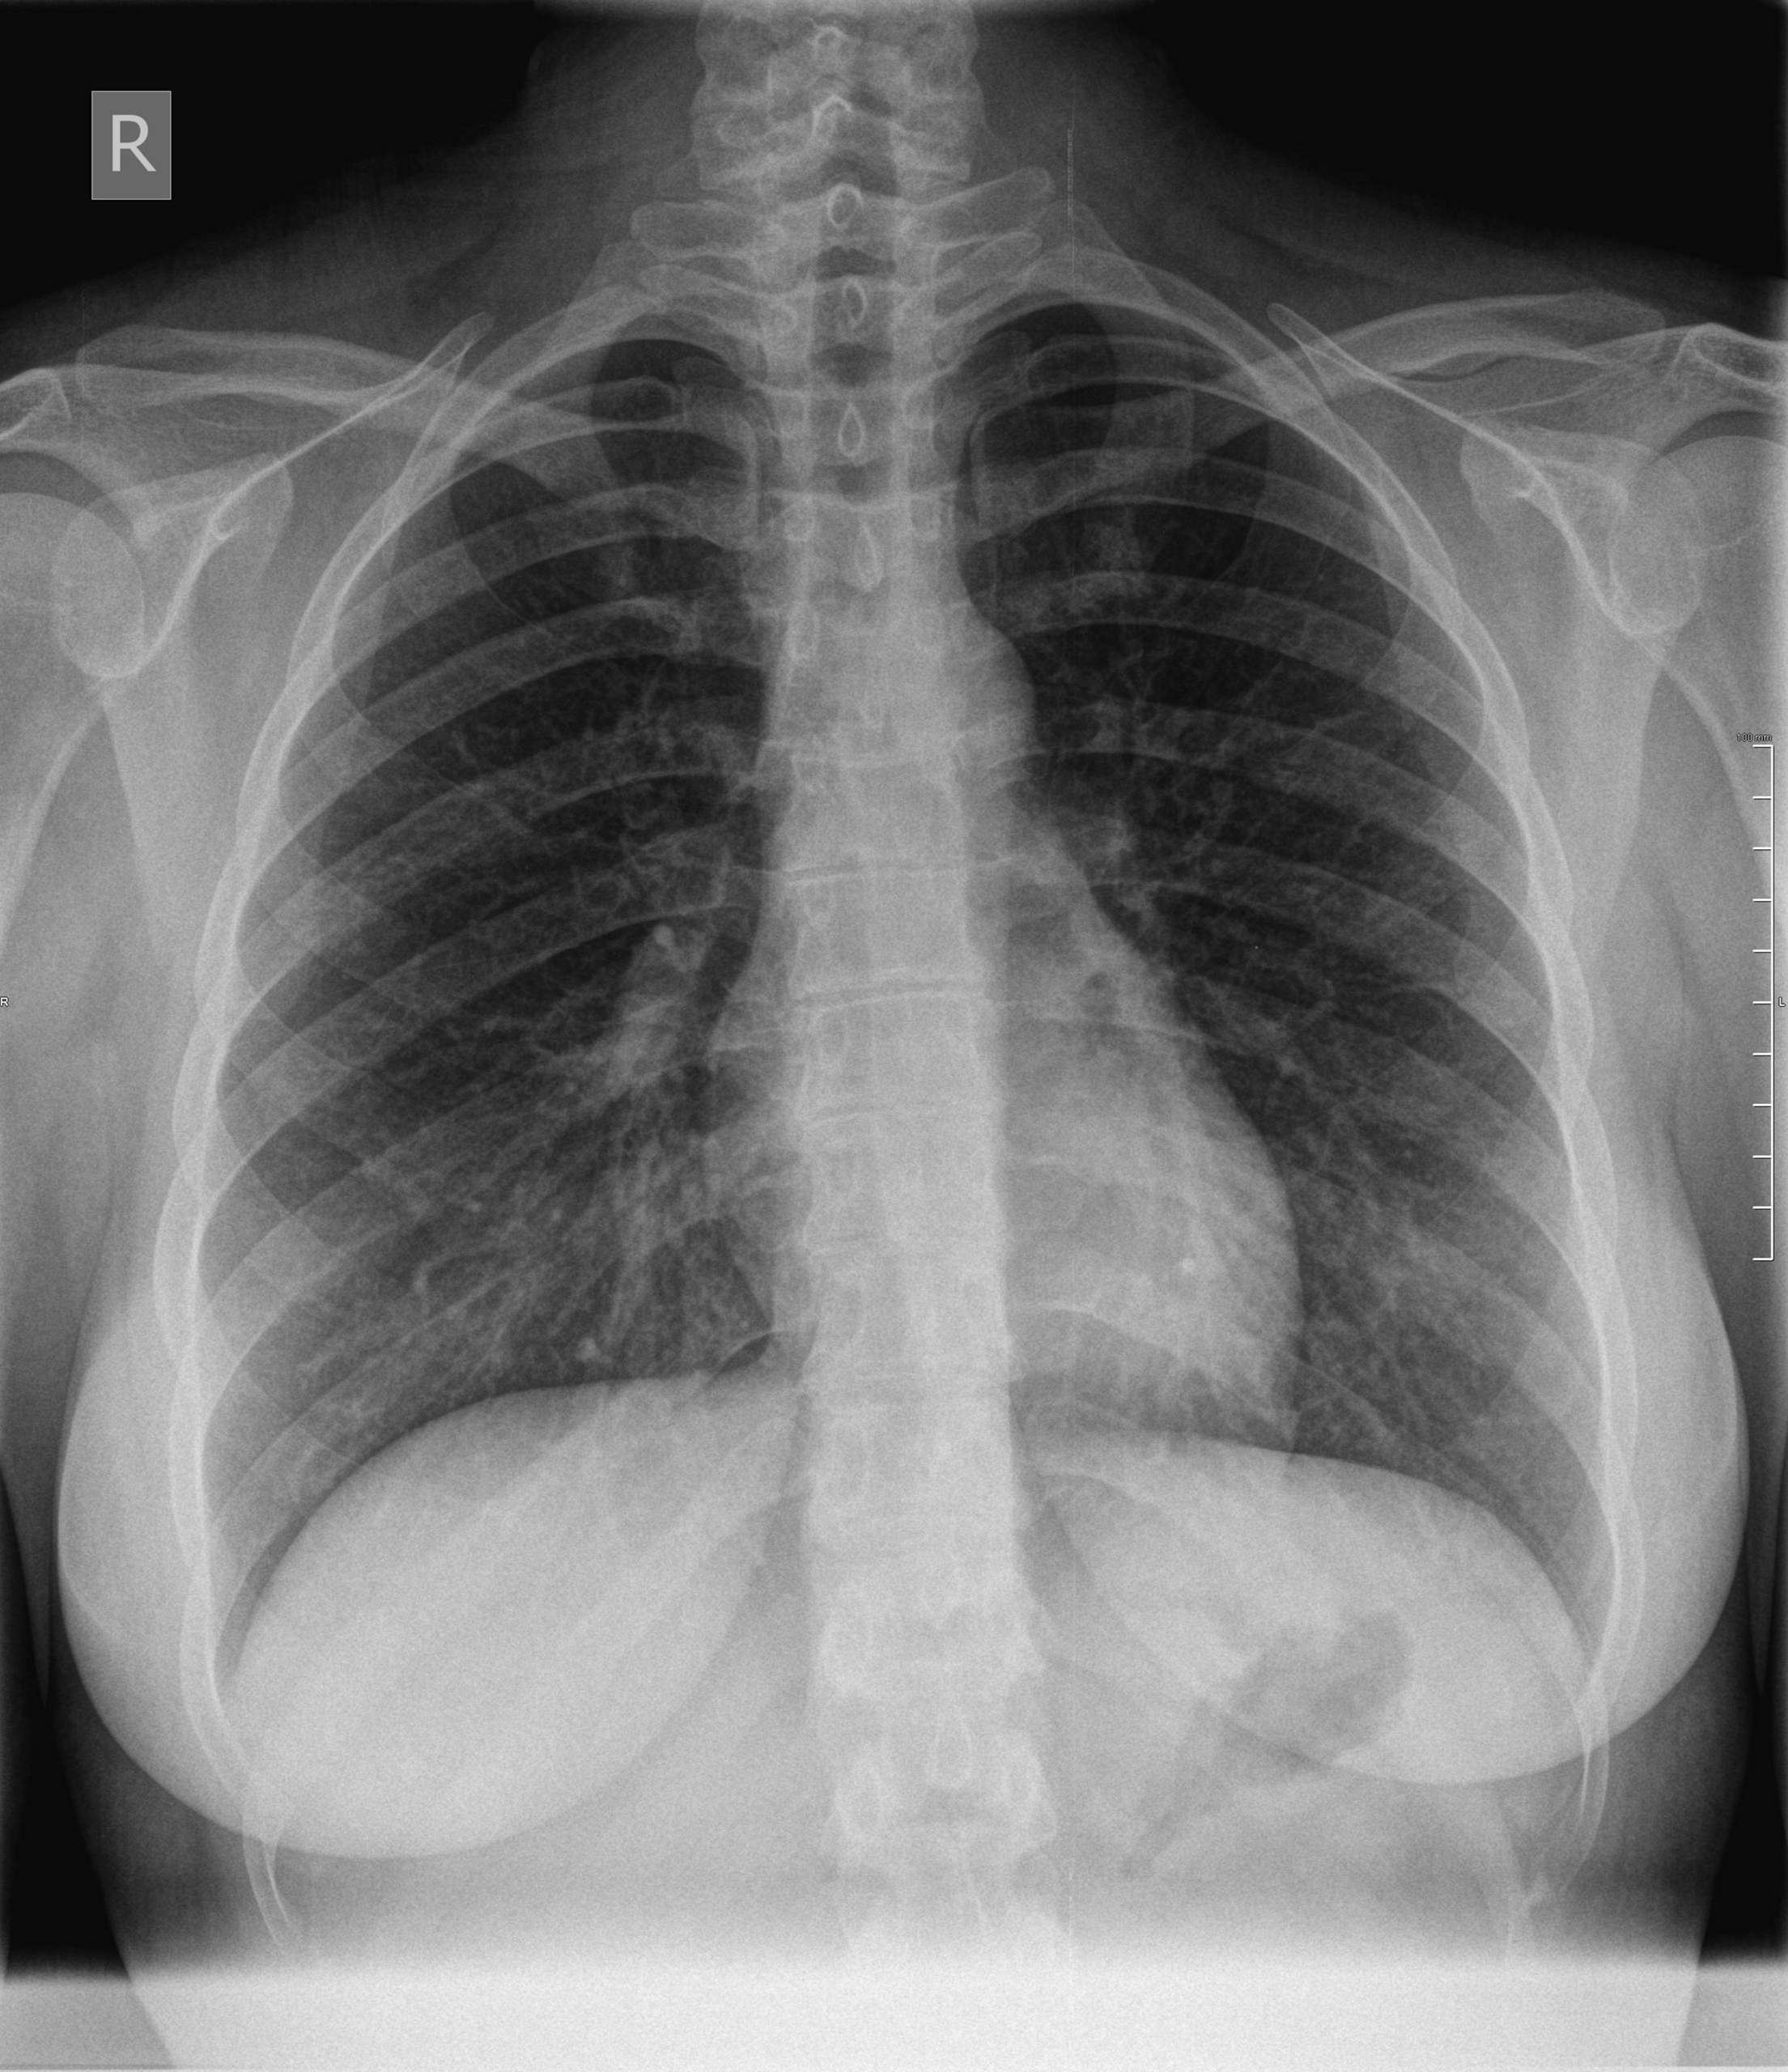

Bei einer Lungenembolie wird ein Blutgerinnsel in eine Lungenarterie eingeschwemmt und kann diese so verstopfen. So gelangt nur unzureichend Sauerstoff ins Blut. Kleine Embolien vergehen oft symptomlos Verschlüsse großer Lungengefäße können im schwersten Falle einen Herz-Kreislauf-Stillstand bewirken.

Bei einer Lungenembolie auch Lungenarterienembolie genannt ist eine Arterie der Lunge durch ein Blutgerinnsel verstopft. Ein typischer Vormittag in der Praxis.

Lungenembolie Anzeichen können je nach Patient und Schwere des Arterienverschlusses variieren.

Lungenembolie Anzeichen können je nach Patient und Schwere des Arterienverschlusses variieren. Ein besonders hohes Thromboserisiko haben bettlägerige Menschen frisch Operierte. In der Folge fällt der Blutdruck ab die Organe werden nicht mehr richtig durchblutet und dem Körper fehlt Sauerstoff. Sind die blutzuführenden Gefäße der Lunge verstopft kann dies eine Lungenembolie auslösen. Bei Herzinfarkt und Schlaganfall verstopft ein Blutgerinnsel ein lebenswichtiges Gefäß im Herzen oder im Gehirn. Bei einer Lungenembolie wird ein Blutgerinnsel in eine Lungenarterie eingeschwemmt und kann diese so verstopfen. Mit dem Blut wurde es anschließend in die Lunge geschwemmt.